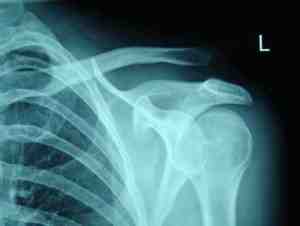

Plan de cuidados enfermero a un paciente diagnosticado de luxación de hombro izquierdo cerrada tras una caída de moto en accidente de tráfico

Recidiva de luxación acromioclavicular

Se presenta el caso de una paciente varón de 30 años que sufre una luxación acromioclavicular izquierda tipo III de Rockwood y Matsen. Es intervenido mediante reducción y fijación con agujas K. Acude a la revisión con una recidiva de la luxación y es reintervenido. Se le coloca un autoinjerto de recto interno desde la clavícula a la coracoides. El postoperatorio transcurre sin complicaciones. En la actualidad el paciente está asintomático y reincorporado a su actividad laboral previa.

Palabras clave: recidiva, luxación, acromioclavicular, autoinjerto.